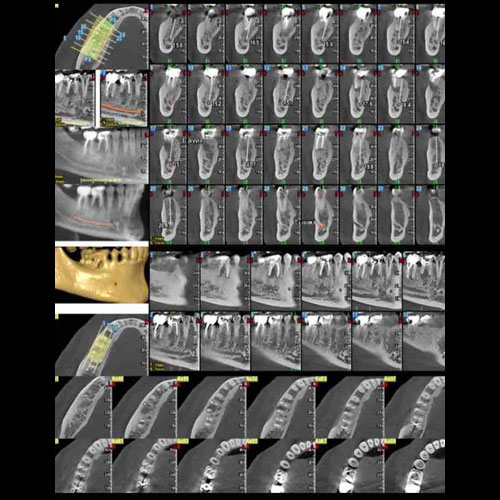

Υπολογιστικά Kαθοδηγούμενη Eμφυτευματολογία-Computer Guided Implantology

Αρχικά λαμβάνεται μία ειδική οδοντιατρική αξονική τομογραφία (CBCT/dental scan). Οι τομές ανασυντίθενται και έτσι είναι δυνατόν, με τη βοήθεια της ψηφιακής τεχνολογίας και ειδικού λογισμικού,να γίνει αναπαράσταση και να κατασκευαστεί ουσιαστικά ένα «ομοίωμα» των οστών της γνάθου.

Ψηφιακή Ροή-Fully Guided Implant Surgery

Στη συνέχεια, με τη βοήθεια κατάλληλου λογισμικού, επιλέγεται το είδος του εμφυτεύματος και οι διαστάσεις του και τοποθετείται αυτό στην ακριβή του θέση στη γνάθο μέσα στο πρόγραμμα.

Στη συνέχεια κατασκευάζεται κατάλληλος χειρουργικός νάρθηκας, και εκτυπώνεται με τρισδιάστατο εκτυπωτή -3D printer- που θα καθοδηγήσει τον επεμβαίνοντα ώστε να τοποθετήσει τα εμφυτεύματα στην ακριβή θέση που έχει προεπιλεγεί μέσα από τον υπολογιστή έχοντας υπόψιν τη θέση των ανατομικών μορίων που θέλουμε να αποφύγουμε και την ποσότητα και ποιότητα του οστού.